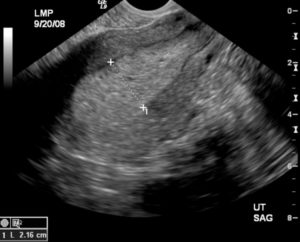

При гиперплазии эндометрия УЗИ проводится с целью изучения изменений, которые произошли в маточной полости, уточнения толщины эндометрия с выявлением очагов патологии и нахождения полипов. Исследование производится специальным датчиком, который вводят женщине во влагалище.

Если при проведении УЗИ выявлено утолщение эндометрия, которое равномерно по значению и оно имеет выраженные контуры, обладая при этом неоднородной эхогенностью, то такие показания являются явным признаком гиперплазии. Кроме того, ультразвуковой метод исследования позволяет выявить наличие полипов.

При диагностике гиперплазии эндометрия делать УЗИ предпочтительно сразу после завершения менструации. Именно на 5-7 дне цикла толщина эндометрия наиболее тонкая.

Поэтому, если полученный результат составляет более 7 мм, то можно предположить наличие гиперплазии, а при показателях 20 мм и выше — велика вероятность, что патологические процессы в эндометрии имеют злокачественный характер.

Проведение УЗИ матки дает возможность получит достоверную информацию о состоянии яичников и возможных патологиях эндометрия. Ультразвуковое исследование эндометрия дает возможность оценить качественные и количественные параметры эндометрия на разных фазах менструального цикла.

Эндометрий отличается большой акустической плотностью. Его толщина увеличивается в зависимости от фазы менструального цикла. Если в первом цикле толщина эндометрия составляет 3-4 мм, то во второй фазе его толщина увеличивается до 1,2-1,5 см.

Признаки гиперплазии эндометрия? По УЗИ проявляются его достаточно равномерным утолщением, однородной эхогенностью и ровными контурами. Для полипов характерными признаками являются новообразования, которые имеют повышенную акустическую плотность, ровные контуры и эхонегативный ободок.

Признаком гиперплазии эндометрия при УЗИ в период менопаузы является увеличение М-эха до 0,5 см и больше.

Для диагностики патологического состояния эндометрия, а также контроля над эффективностью лечения, проведение Узи эндометрия назначают на 5-6-й день менструального цикла.

Достоверность и точность обследования подтверждается показателями и составляет 91% при диагностике гиперплазии, 60-80% — при диагностике полипов эндометрия. Пройти обследование УЗИ можно в нашей клинике.

УЗИ дает показатели, которые должны вписываться в нормы относительно определенной менструальной фазы.

Слизистый слой эндометрия имеет четкие очертания и значительную акустическую плотность по сравнению с мышечным слоем, то есть с миометрием. На толщину слизистой оболочки оказывает влияние месячный цикл.

В первой фазе стенка всего 3-4 мм, во второй фазе показатель равен 12-15 миллиметров.

Признаки гиперплазии эндометрия по УЗИ: равномерное по значению утолщение с выраженными ровными контурами и однородной эхогенностью.

Чтобы определить тип гиперплазии и проконтролировать, насколько помогает лечение, делают УЗИ на 5-7-й день месячного цикла. Точность исследования выявленных гиперпластических трансформаций составляет 90%, а обнаруженных полипов эндометрия – 60-80%.

Информативность скринингового метода может быть различной, что зависит от рабочих характеристик самого аппарата, опыта врача-диагноста и возраста больной. Эхографические признаки гиперплазии эндометрия включают ниже перечисленные:

- полипы размером 16,1-17,5 мм

- срединная маточная структура толщиной от 14,6 до 15,4 мм

- аденокарциному подозревают при показателях 19,7-20,5 мм

Гиперплазия в постменопаузальный период диагностируется, если величина М-эхо 5 и выше миллиметров.

Ультразвуковое исследование органов малого таза с использованием трансвагинального датчика позволяет выявить патологию, основываясь в первую очередь на таком показателе, как М-эхо матки.

Важно понимать, что величина его не является постоянной и изменяется в зависимости от дня цикла.

Исходя из этого, выделяют 4 степени М-эха матки, характерные для ранней и поздней стадии пролиферации, периовуляторного периода, а также секреторной фазы.

Помимо этого, диагностическую ценность имеет результат определения срединного М-эха, позволяющий определить плотность слизистой оболочки.

- Утолщение эндометрия (при проведении исследования на 5-7 день цикла показатель м-эха превышает 14,5 мм; в периоде постменопаузы в любой день – более 5 мм)